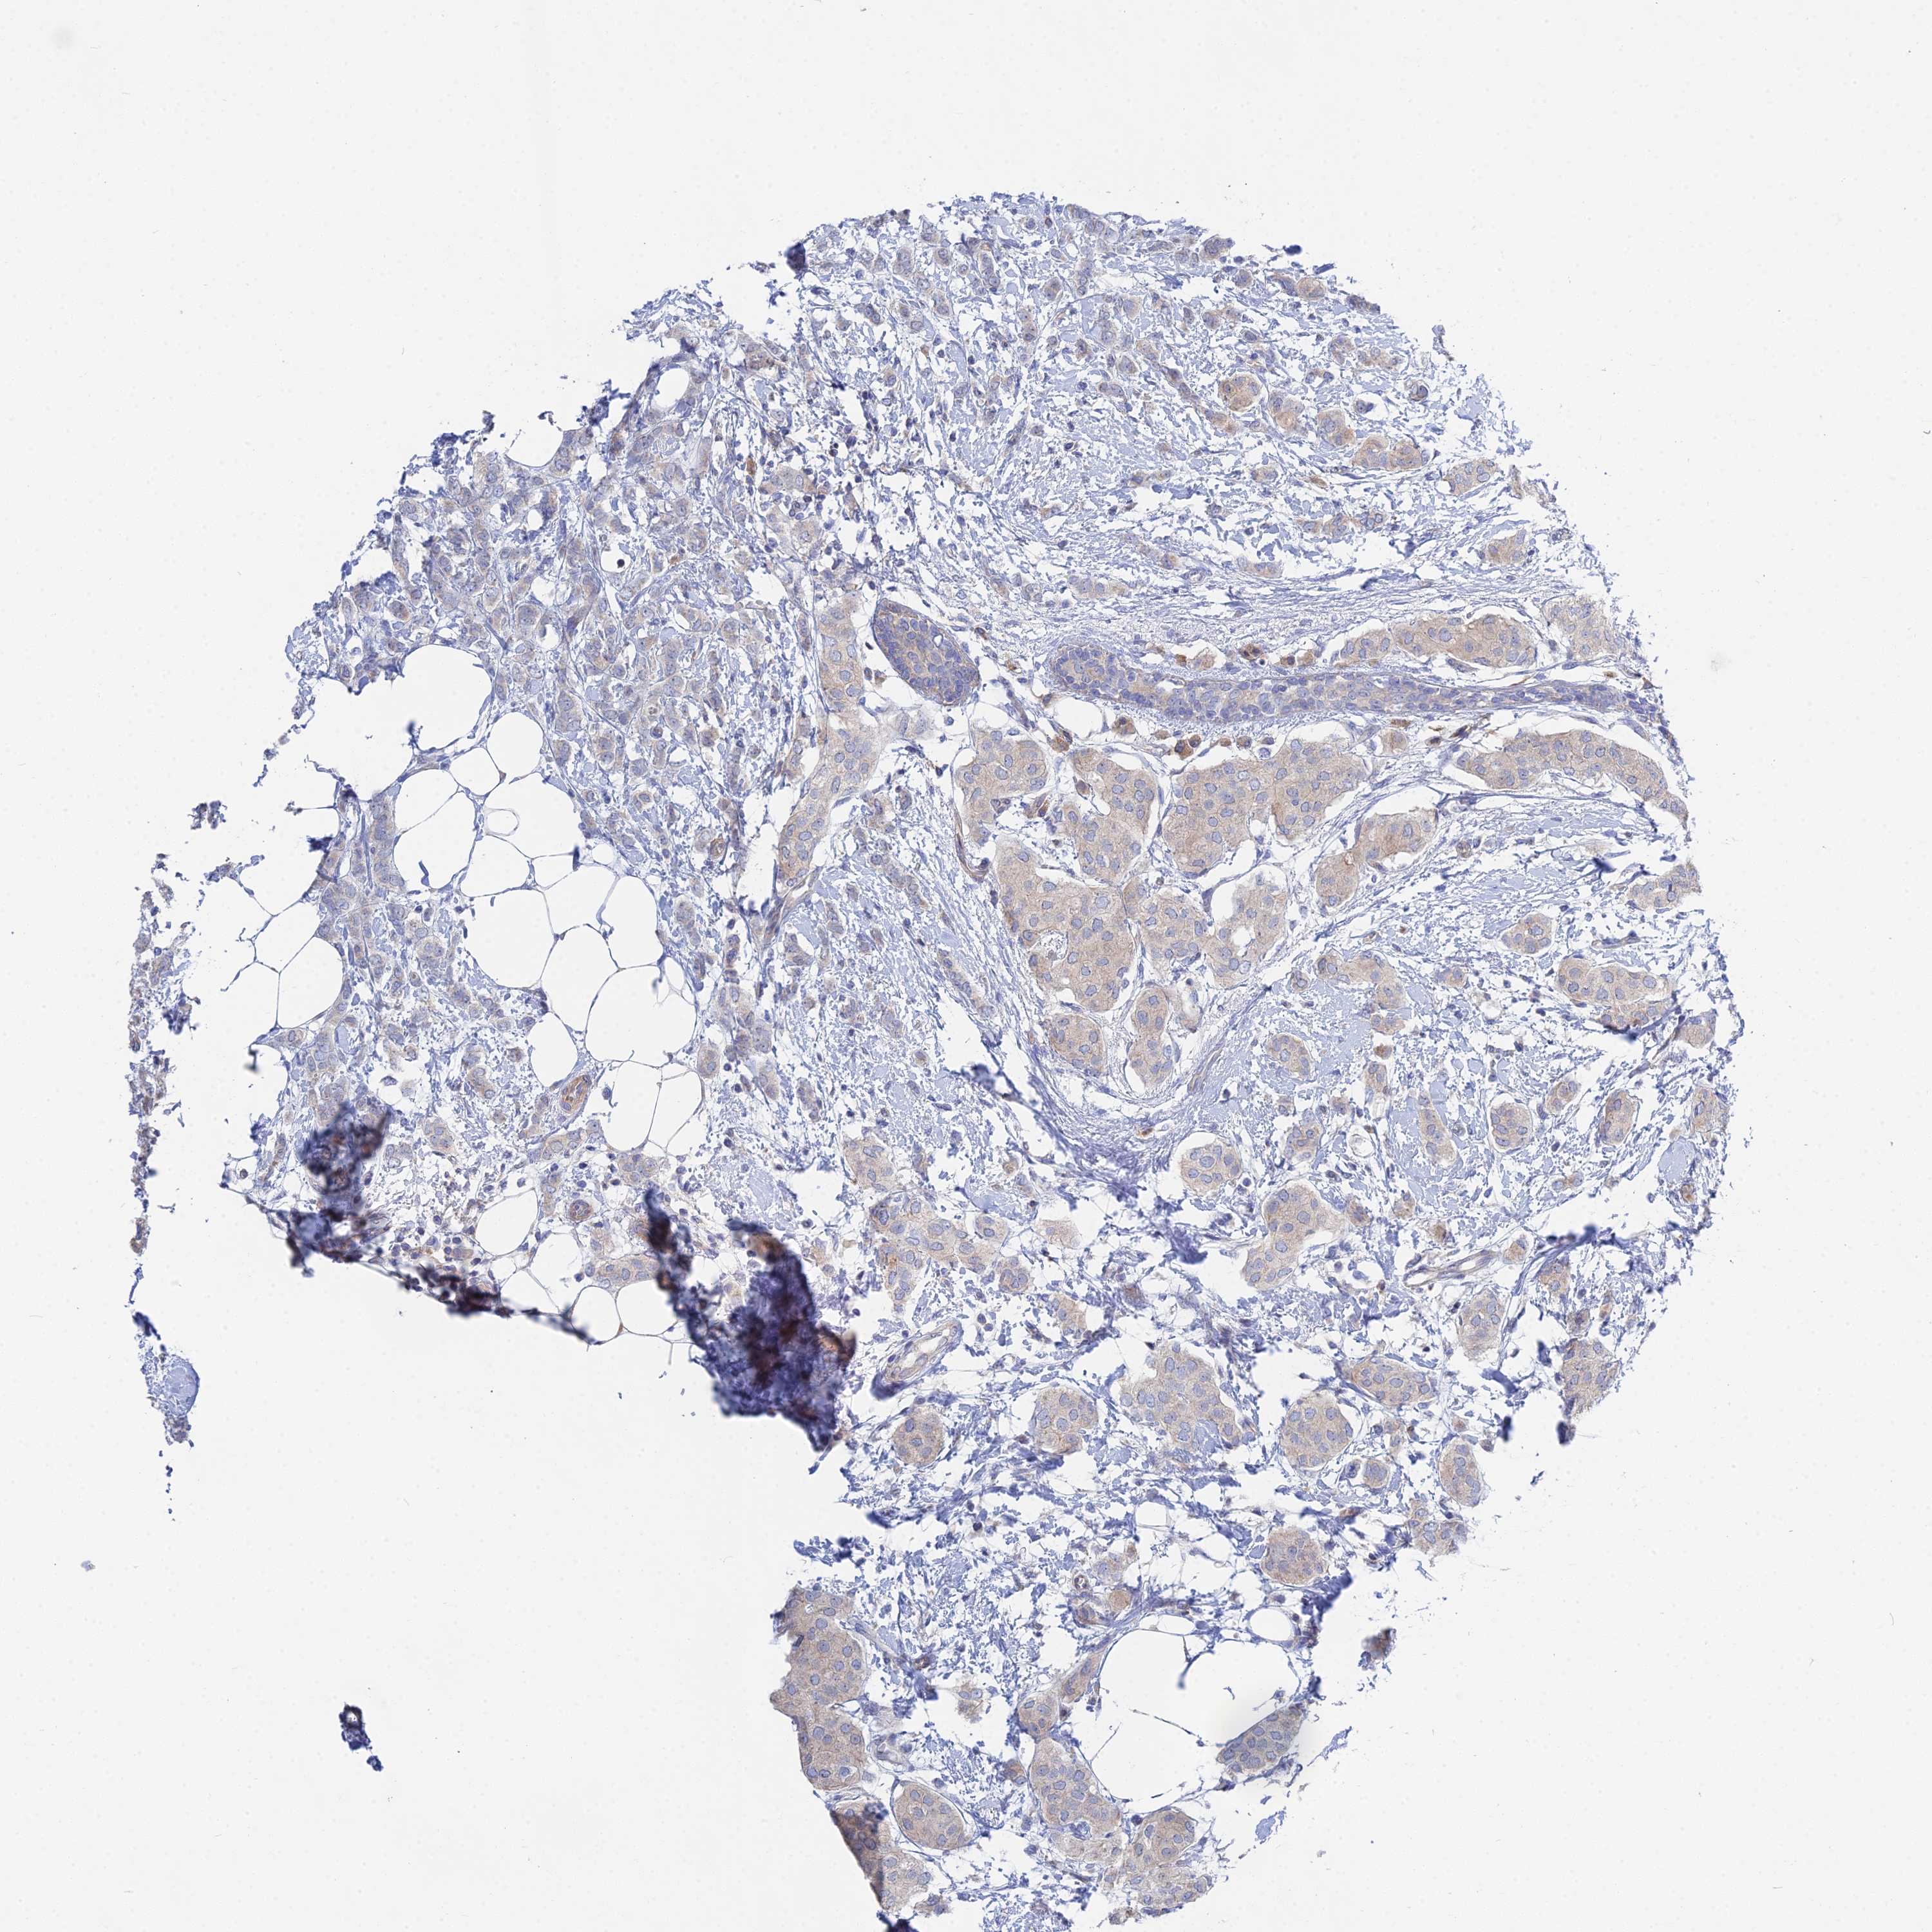

BRCA TCGA BRCA VALIDATION PROTEIN EXPRESSION

ANTIBODIES

AND

VALIDATION